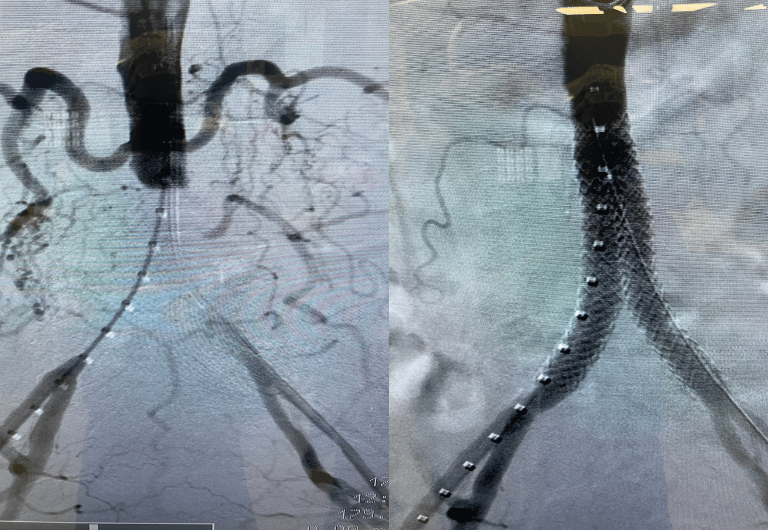

EVAR (Reparación Aórtica Endovascular): Tratamiento del aneurisma de aorta abdominal mediante endoprótesis (acceso femoral, recuperación acelerada).

Síndrome Aórtico Agudo (Disección Tipo B): Tratamiento endovascular de la aorta torácica (TEVAR) para el manejo de disecciones complicadas, úlceras penetrantes y hematomas intramurales.